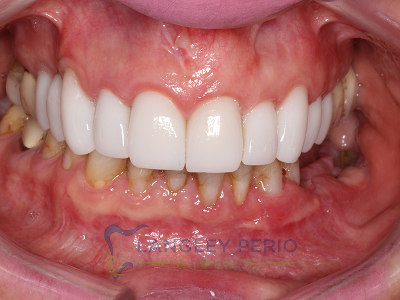

Case 3

Alloderm tissue grafting performed to improve root coverage and esthetics. This technique does not require tissue to be taken from the patient’s palate.